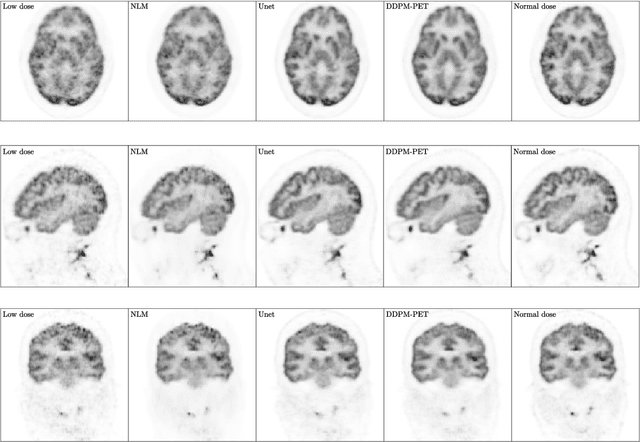

Abstract:Due to various physical degradation factors and limited counts received, PET image quality needs further improvements. The denoising diffusion probabilistic models (DDPM) are distribution learning-based models, which try to transform a normal distribution into a specific data distribution based on iterative refinements. In this work, we proposed and evaluated different DDPM-based methods for PET image denoising. Under the DDPM framework, one way to perform PET image denoising is to provide the PET image and/or the prior image as the network input. Another way is to supply the prior image as the input with the PET image included in the refinement steps, which can fit for scenarios of different noise levels. 120 18F-FDG datasets and 140 18F-MK-6240 datasets were utilized to evaluate the proposed DDPM-based methods. Quantification show that the DDPM-based frameworks with PET information included can generate better results than the nonlocal mean and Unet-based denoising methods. Adding additional MR prior in the model can help achieve better performance and further reduce the uncertainty during image denoising. Solely relying on MR prior while ignoring the PET information can result in large bias. Regional and surface quantification shows that employing MR prior as the network input while embedding PET image as a data-consistency constraint during inference can achieve the best performance. In summary, DDPM-based PET image denoising is a flexible framework, which can efficiently utilize prior information and achieve better performance than the nonlocal mean and Unet-based denoising methods.